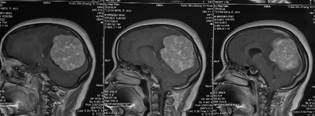

术前影像